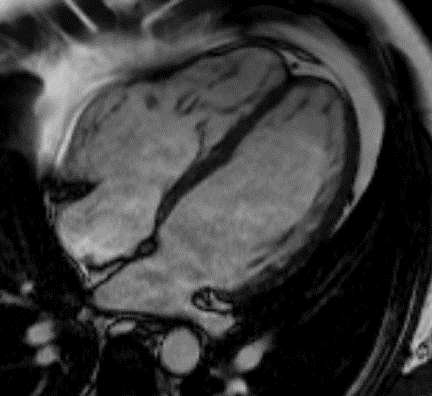

Μαγνητική Τομογραφία Καρδιάς - Heart MRIΗ μαγνητική τομογραφία καρδιάς είναι μια εξειδικευμένη ιατρική απεικονιστική μέθοδος για την μη επεμβατική αξιολόγηση της μορφολογίας και της λειτουργίας της καρδιάς. Χρησιμοποιεί μαγνητικά κύματα υπό ηλεκτροκαρδιογραφικό συντονισμό για τη παραγωγή υψηλής ευκρίνειας στατικών αλλά και δυναμικών εικόνων της καρδιάς και των μεγάλων αγγείων αυτής, χωρίς τη χρήση ιονίζουσας ακτινοβολίας. Με βάση τις εικόνες αυτές, μπορεί να πραγματοποιηθεί με υψηλή αξιοπιστία η διάγνωση και να σχεδιαστεί λεπτομερώς η θεραπεία των περισσοτέρων παθήσεων της καρδιάς.